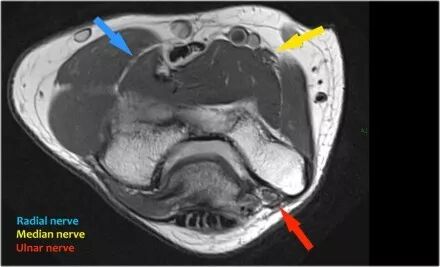

尺神经:在这里,我们看到了肘管内的尺神经。尺骨侧支带的后带形成隧道的底部,而支持带形成屋顶。

该患者有尺神经神经病变。肘管综合征是一种常见的周围神经病变。它产生于肘管内尺神经,其中该神经传递肘管支持带的下方的压缩。

桡神经:在桡骨头水平可以最好地识别桡神经,在那里你可以看到桡骨隧道中的浅表和深支(箭头)。这是寻找桡神经的非常一致的地方。

中位神经:正中神经落后于Lacertus纤维,即肱二头肌的腱膜并穿透旋前肌。